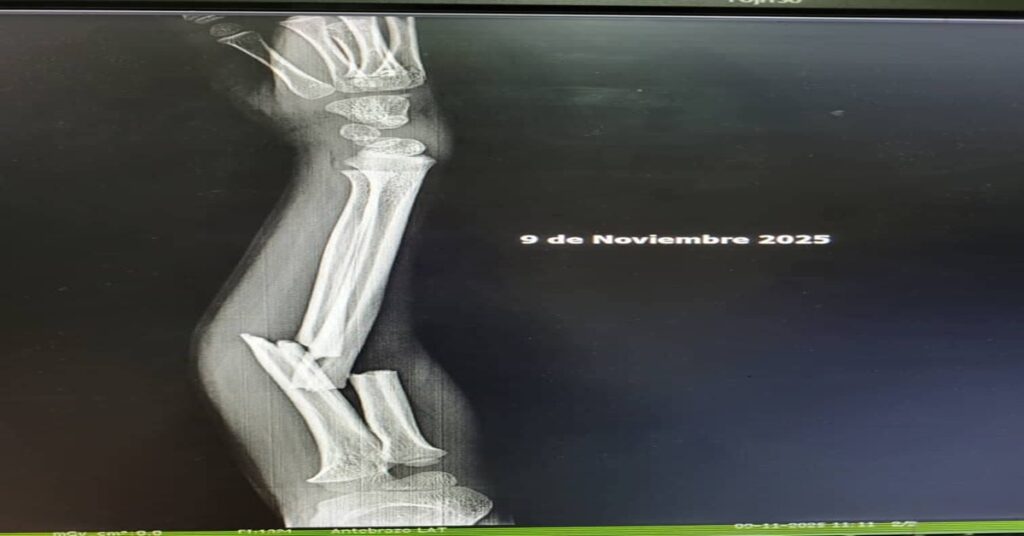

En el hospital Leopoldito Martínez, según la denuncia, la situación fue kafkiana: ingreso remitido “directo para el salón por una fractura en el brazo”, instrucciones contradictorias, personal que acusa al equipo de ambulancias y ambulancieros que señalan a los médicos, mientras el paciente queda flotando entre responsabilidades ajenas. Peor aún: la ambulancia, esa promesa móvil de auxilio, aparece por la ciudad como un patrimonio privado y no servicio público; se usa “para todo menos para llevar pacientes”, escribe la madre con la desesperación y la vulgaridad que da el estar al borde del llanto. Esa crudeza del lenguaje es, precisamente, el pulso que tiene hoy la calle y que conviene oír sin filtros.

(«Gracias a todos por no dejar que mi situación quedará impune. Yo soy una persona solidaria, pero a uno le duele lo de uno. Ya mi hijo acaba de salir del salón, una operación de casi tres hora, el peor momento de mi vida. Le pusieron dos varillas y tuvo dos picaduras en el brazo; espero que con el favor de Dios salir rápido de esto. Que diosito me lo siga protegiendo. Gracias a todos», escribió Fonseca)